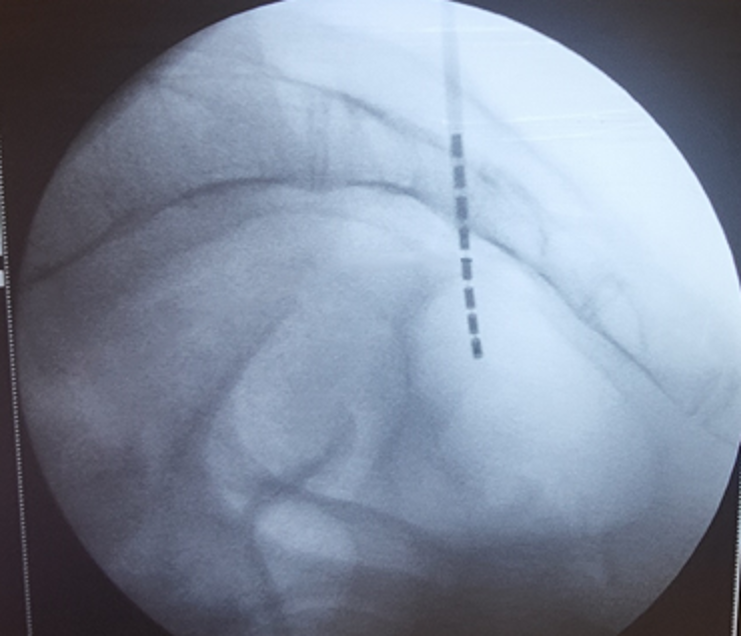

Пациенткам обеих групп проводилась имплантация электродов для стимуляции крестцовых корешков через отверстие S3 с одной или двух сторон (рис.1,2), или в крестцовый канал трансхиатально или ретроградно в зависимости от анатомии крестца и клинической картины. На выбор стороны стимуляции влияли такие факторы как степень развития крестцовых отверстий, желание и образ жизни пациента, визуализируемость отверстия S3 на рентгене. Значимой разницы в эффективности стимуляции в зависимости от стороны стимуляции нами выявлено не было. Необходимо отметить, что двустороннюю стимуляцию мы применяли только в 2 случаях, когда недержанию сопутствовала двустороння тазовая боль. В случае боли с одной стороны, электрод устанавливали с той же стороны, при отсутствии боли, у женщин только АИ сторона определялась вышеназванными факторами.

Рис 2. Рентгенограмма крестца в боковой проекции. Электрод располагается между 3 и 4 крестцовыми позвонками